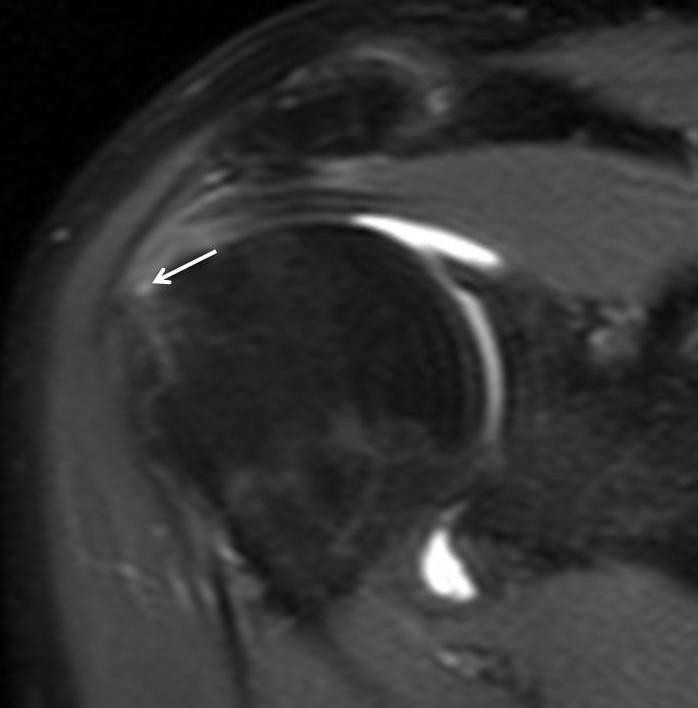

Figure 3

Proton Density FS-weighted sequence (TR/TE/Thick: 4011 ms/7,272 ms/4 mm) on oblique coronal plane, after administration of dimeglumine salt of gadopentetate acid diluted in saline solution at 2 mmol/l concentration. Supraspinatus tendon partial tear on articular side was confirmed (point white arrow).